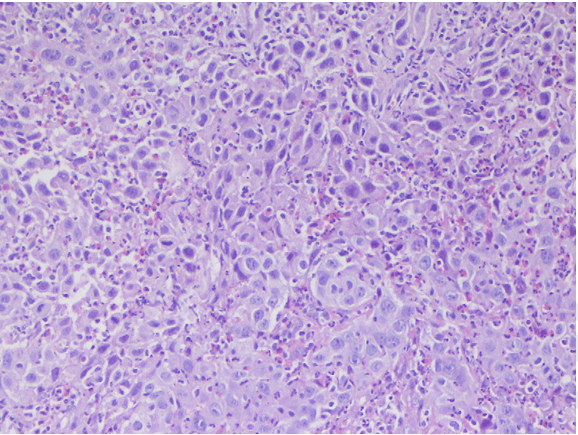

Microscopic examination of the biopsied specimen of the tumor revealed sheets of large cells with abundant inflammatory infiltration consisting predominantly of eosinophils and lymphocytes characterized by large nuclei with prominent nucleoli. Cells showed a moderate amount of granular or clear cytoplasm. We observed a high mitotic rate and many abnormal mitoses and distinct cell membrane stained well by PAS stain. Finally, the presence of necrosis area was noted. The pathological diagnosis of glassy cell carcinoma was made (Figure 1) (Figure 2) (Figure 3).

Figure 1: Microscopic examination of the biopsied vaginal tumor showing glassy cells organized in nests separated by stroma infiltrated with eosinophils (H&E stain, x100).

Thus, the diagnosis is pathological. Histologically, the glassy cell carcinoma is composed by cells arranged in nests and cords separated by fibro vascular septa. The stromal infiltration is predominantly composed of eosinophil cells and plasma cells with an admixture of lymphocytes, giving a very characteristic appearance.

The cytoplasm's cells are eosinophilic, sometimes amphophilic, with a ground glass appearance and distinct cell membrane stained well by PAS stain. The nuclear membrane is dense. The majority of the nuclei are large, vesicular and hyper chromatic, round to oval, containing exceptionally large and prominent nucleoli [2][3].

Mitotic activity is important with cellular pleomorphism and numerous abnormal mitoses. Focal squamous or glandular differentiation may be seen but not in the reported case. Small foci of necrosis are frequently present as shown in the related case.